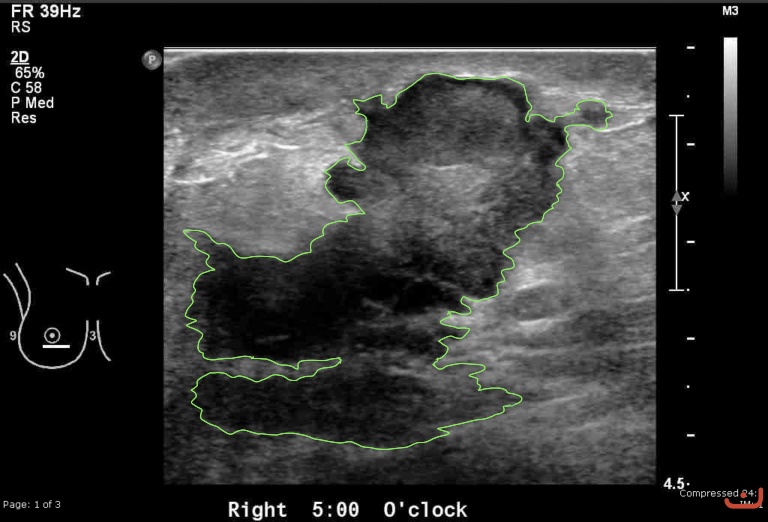

Case 44-G1

Malignant solid mass

Friday, 22 May 2015

206.17 KB (768 x 522 px)